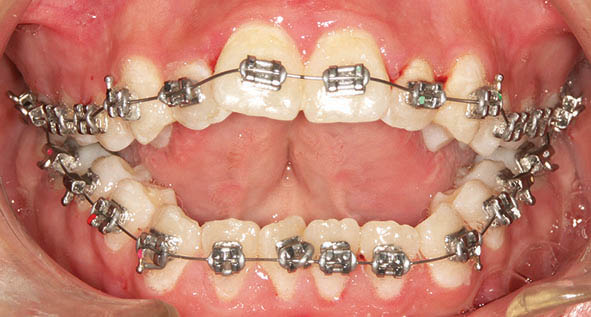

در بیمار اپن بایت (شکل 38-3 الی 40-3) در هر دو سمت چپ و راست یک مینی اسکرو در سمت باکال (شکل 41-3 الی 43-3) و یکی در سمت پالاتال (شکل 47-3) قرار میدهیم. آرچ وایری که میگذاریم را در ناحیه بین کانین و پرمولر اول قطع میکنیم تا دندانهای خلفی با قدامی روی یکدیگر اثری نداشته باشند. وقتی آرچوایر سه تکه باشد دندانهای سگمنت قدام و خلف جداگانه مرتب میشوند. چهار قطعه چین الاستیک از مینی اسکرو باکال به براکت دندانهای پرمولرها و مولرها میاندازیم. چون گردن مینی اسکروها برای چهار قطعه چین الاستیک کوچک است، لذا یک سیم لیگاچور از درون این چهار قطعه چین الاستیک رد میکنیم و آن سیم لیگاچور را به مینی اسکرو درگیر میکنیم تا یک نیروی اینترود کننده روی سمت باکال سگمنت خلفی اعمال شود. از سمت پالاتال هم چند باتن میچسبانیم و همین کار را در سمت پالاتال انجام میدهیم. البته در شکل 41-3 الی 43-3 دندانها در سمت باکال زیادتر از سمت پالاتال اینترود شدند، لذا سمت باکال با سیم لیگاچور به مینی اسکرو وصل شده تا در همان وضعیت بماند.

طی جلسات بعدی سمت پالاتال هم به اندازه باکال اینترود میشود تا نهایتاً درمان تمام گردد (شکل 44-3 الی 46-3).

شکل 41-3

شکل 42-3

شکل 43-3

شکل 41-3 الی 43-3: اینترود کردن سگمنت خلفی به کمک مینی اسکرو در سمت باکال منجر به اینترود بیشتر در سمت باکال و کمتر در سمت پالاتال میشود.